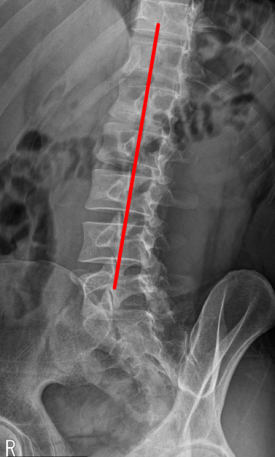

어깨 충돌증후군 & 회전근개파열양쪽 발목 골절 & 인대 완전파열SLAP 파열 & 일자허리일자목 & 디스크 팽륜햄스트링 파열대퇴사두근 파열

SLAP 파열 & 일자허리